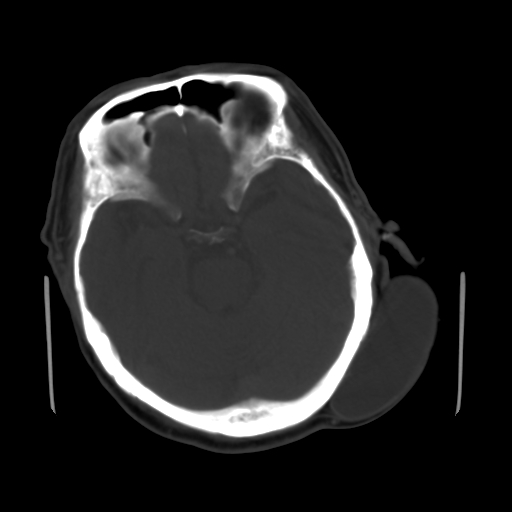

标题: CT25147:男,62岁,右侧肢体活动障碍不灵活三天。 [打印本页]

男,62岁,右侧肢体活动障碍不灵活三天,左侧头皮肿物十余年(ct值8hu)。

1)多发性腔隙性脑梗塞。2)脑白质病。3)脑萎缩。4)左侧枕顶部头皮下皮样囊肿,不排除脂肪瘤。

1)多发性腔隙性脑梗塞。2)脑白质病。3)脑萎缩。4)左侧枕顶部头皮下皮样囊肿或表皮样囊肿。